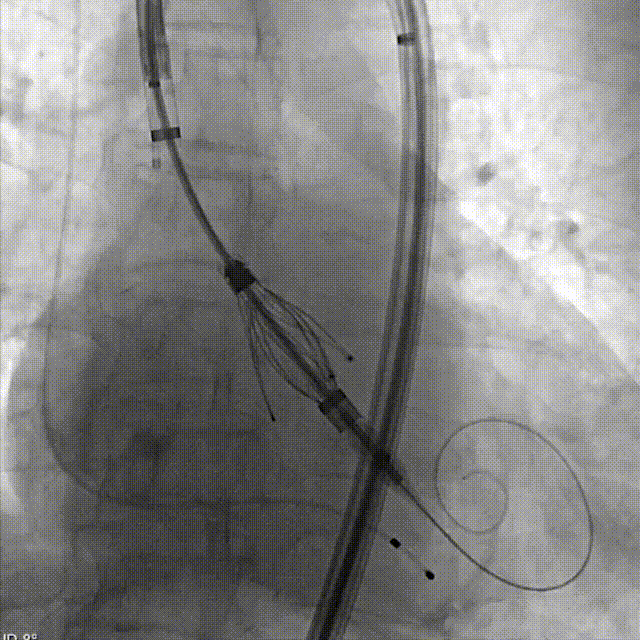

术中影像

定位键与原生窦对齐

依次三窦内造影确认深度

THV释放